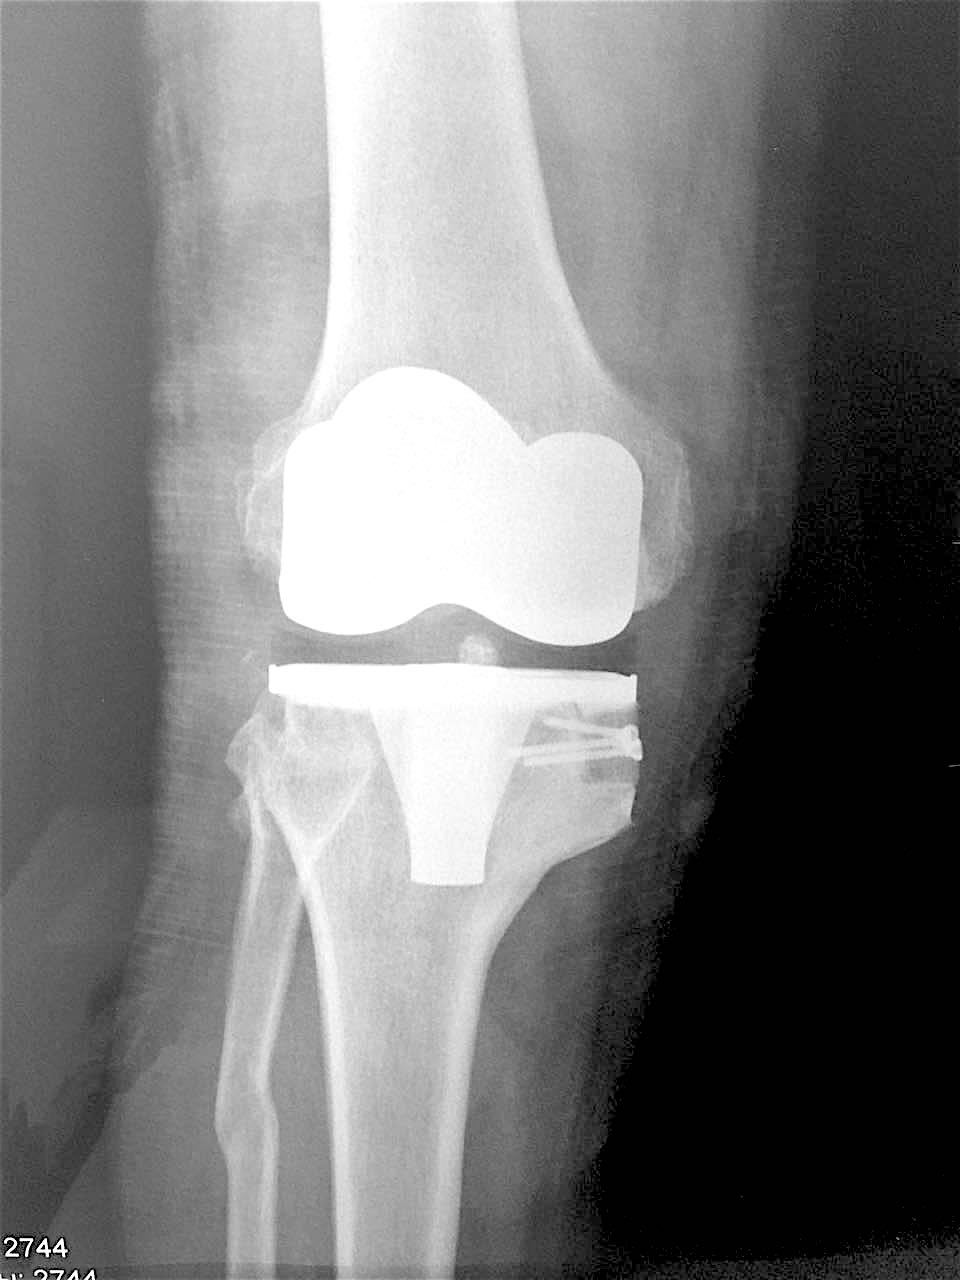

Больной З. 72 года. Диагноз: посттравматический деформириующий правосторонний гонартроз, genu valgum.

Сделано тотальное эндопротезирование коленного сустава, костная аллопластика материалом «Лиопласт».